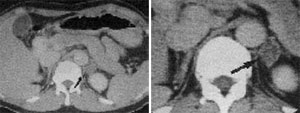

신장은 인체의 대사 노폐물을 제거하고 수분 및 전해질 균형을 유지하는 중요한 역할을 합니다. 신장에 문제가 발생하면 체내의 여러 기능이 부정적인 영향을 받을 수 있습니다. 복부 CT는 신장 결석, 신장 종양 및 기타 신장 관련 질환을 진단하는 데 도움을 줍니다.

신장 결석: 예방법과 치료 방법

신장 결석은 신장에서 형성된 경결된 물질로, 통증을 유발할 수 있습니다. 복부 CT는 결석의 위치와 크기를 정확하게 파악할 수 있으며, 이 정보를 바탕으로 적절한 치료 방법을 결정하는 데 매우 중요합니다. 결석이 발견되면, 물리치료, 약물 치료, 혹은 필요 시 수술이 고려될 수 있습니다. 신장 결석은 수분 보충과 균형 잡힌 식사를 통해 예방할 수 있으므로, 생활 방식의 변화 또한 동반되어야 합니다.